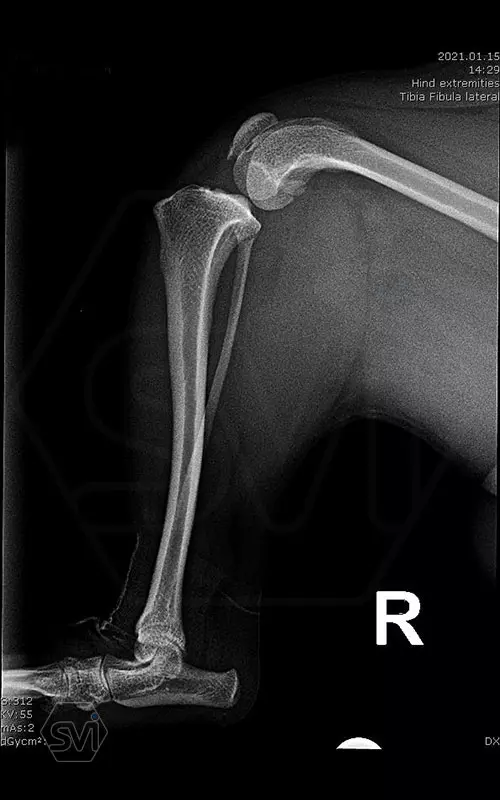

In small dogs, medial patella luxation (MPL) and the rupture of anterior cruciate ligament (RACL) often occur simultaneously. During the surgical procedure, the joint must be stabilized and the patella fixed in the middle axis at the same time.

Between October 2020 and December 2021, we performed 19 TPLO-M surgeries at the Animal Hospital in Nyíregyháza,: 16 times used the mini (2.0 R12) and 3 times the small (2,4 R15) TPLO-M plate.

The experience is very encouraging, we find the system and plates suitable for the simultaneous treatment of MPL and RACL. ( in case of 4/4 pat. lux. also). We will back soon with details.